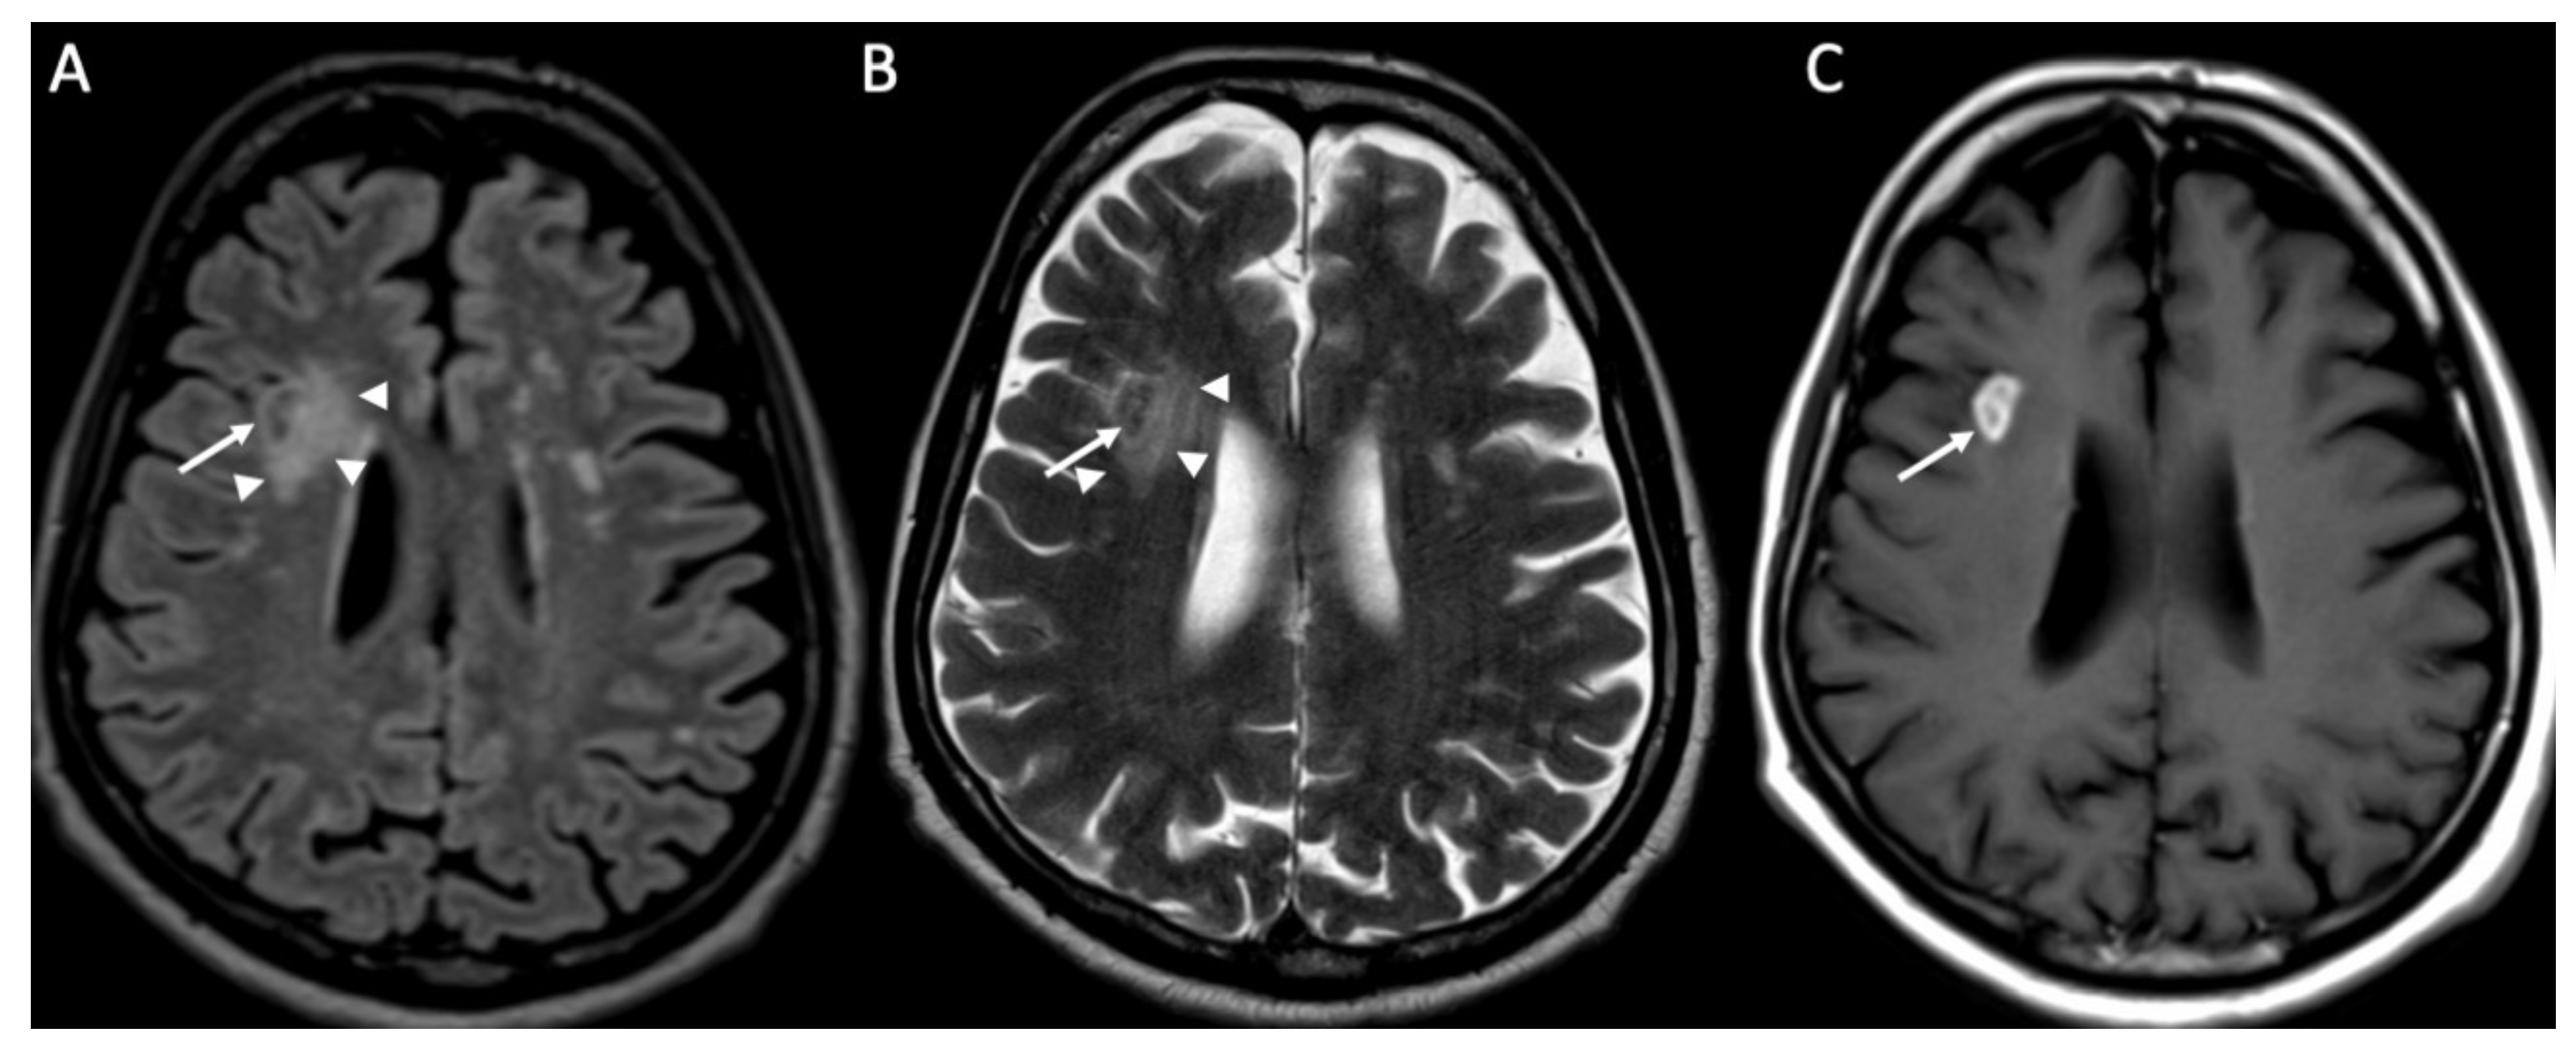

Miliary tuberculomas are frequently seen in patients with tuberculous meningitis [9]. It is characterized by the presence of multiple tiny lesions (with a diameter ranging from 2 to 5 millimeters), whose signal is hypointense on T2, show homogeneous contrast enhancement, and are frequently surrounded by vasogenic edema (Figure 10).

Figure 10.

Axial FLAIR (A,B) and enhanced T1 (C,D) depict multiple tiny foci of enhancement, some of which have a ring appearance (arrows in C,D) in a patient with miliary tuberculosis. They are surrounded by vasogenic edema (arrowheads in A,B).